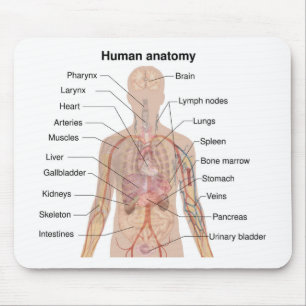

Anatomi i mänskliga organ vykort

Pris23,00 kr

Anatomi i mänskliga organ poster

Pris229,00 kr

Anatomi i mänskliga organ canvastryck

Pris1 425,00 kr

Anatomi i mänskliga organ hälsningskort

Försäljningspris 49,00 kr. Ursprungligt pris 54,00 kr.